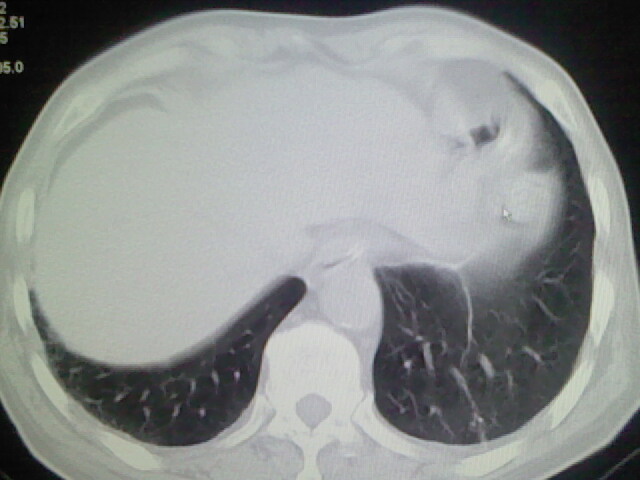

男,70岁,脑出血,长期卧床,左侧背部可触及肿块

考虑右肺及左肺下叶炎症。

右肺及左肺下叶炎症。

考虑右肺及左肺下叶慢性炎症。

肺部感染,背部筋膜增厚,考虑坠积性水肿或炎症

右侧肺部见片状密度增高影,边缘模糊。考虑炎症。另食管壁增厚。